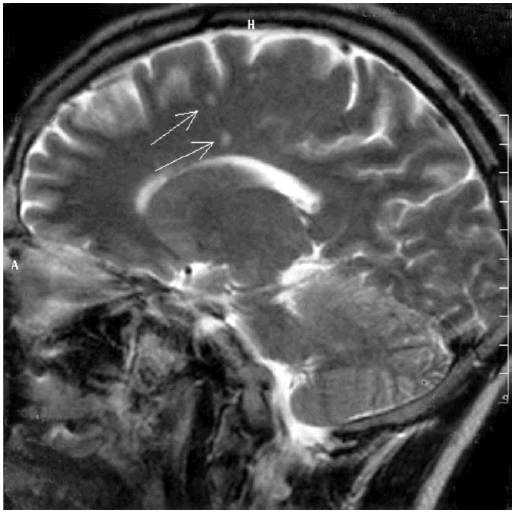

Спустя семь лет было установлено, что эпидемическая вспышка в городе Лайм была вызвана особым возбудителем, которого назвали боррелией, а заболевание – болезнью Лайма, или клещевым боррелиозом. Болезнь распространена не только в США (в 2001 г. зарегистрировано 17 029 случаев), но и в европейских странах (ежегодно около 60 тыс. случаев), в том числе в России. При клещевом боррелиозе через 2–4 недели от присасывания клеща у 40 % пациентов в Европе и у 80 % больных в США возникают кожные проявления. Обычно это кольцевидная эритема, одно или несколько красных пятен в месте присасывания клеща, подъем температуры тела, головная боль, тошнота. Нам приходилось наблюдать и диссеминированные формы. Позднее может развиваться серозный менингит, поражение лицевого нерва, ухудшение зрения, боли в области суставов, сердца. Необходимы срочная госпитализизация в остром периоде, проведение антибактериальной терапии по поводу клещевого боррелиоза, тогда полное выздоровление наступает у 70 % больных. Нередко клещ является носителем клещевого энцефалита и клещевого боррелиоза одновременно. После укуса клеща высока вероятность заражения клещевым боррелиозом (в природных очагах 20–50 % клещей – носители боррелий). Опыт сотрудников кафедры инфекционных болезней Военно-медицинской академии по профилактике и лечению клещевого боррелиоза изложен в книге «Лайм-боррелиоз (иксодовые клещевые боррелиозы)» Ю. В. Лобзина, А. Н. Ускова, С. С. Козлова [110]. Если от момента укуса клеща прошло меньше трех суток, рекомендуют антибиотик доксициклин в дозе 0,1 в таблетках один раз в день в течение пяти дней (можно детям старше восьми лет); если этот временной период превышен, то профилактический курс следует продлить до десяти дней. Такой подход позволяет предупредить развитие клещевого боррелиоза и переход его в хронические формы заболевания. Вопрос о хроническом клещевом боррелиозе в настоящее время широко обсуждается. Доказано, что Borrelia burgdorferi может персистировать в нейронах и глиальных клетках длительное время. При этом пенициллин, цефтриаксон, доксициклин не обладают эффективностью против этих бактерий в хронической форме, когда они представлены в виде цист [321]. У пациентов с множественными очагами демиелинизации по данным МРТ головного мозга выявляются когнитивные расстройства [290]. Приводим МРТ головного мозга пациента 37 лет с нейроборрелиозом, у которого развилась картина умеренной деменции (рис. 9.2).

Рис. 9.2. МРТ головного мозга пациента с нейроборрелиозом. Множественные очаги демиелинизации